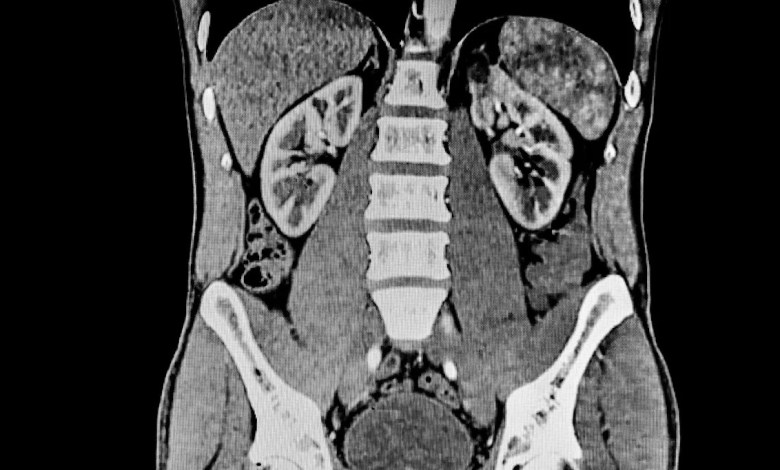

It was also discovered that the physicochemical properties of polyamide affect how it is distributed in the body after digestion, and that microplastics accumulate in organs such as the liver.